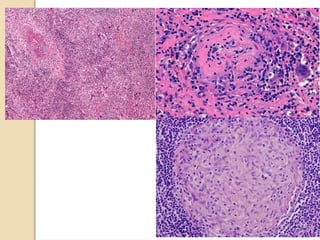

Morphology

 Transmural mononuclear cells

infiltration

 Perivascular infiltration of vasa vasorum.

 Intima : Marked thickening and luminal

narrowing.

 Media : Granulomatous change with

central necrosis , Langhan’s giant cells and

mononuclear inflammatory cells.

 Adventitia : mononuclear cell infiltration

A. Intimal fibrosis

B. Fibrosis of media and infiltration of inflammatory cells around vasa vasorum.

C. and D. Inflammatory cell infiltrate consists of predominantly mononuclear lymphocytes.